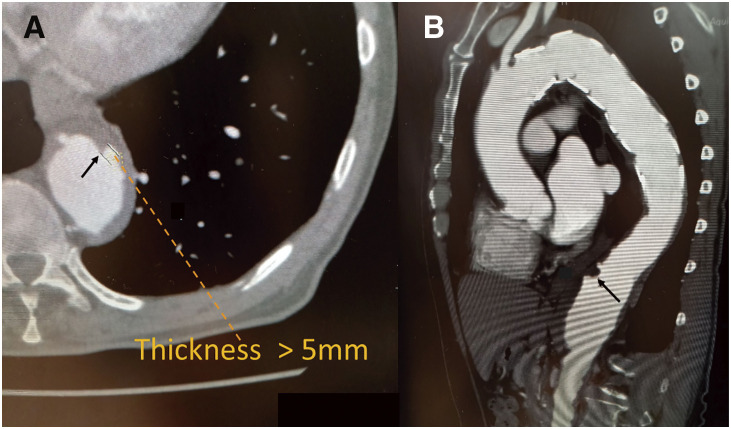

Objective: In open repair for descending thoracic aortic aneurysm (DTAA) or thoracoabdominal aortic aneurysm (TAAA), the influence of re-interventions on spinal cord injury (SCI) remains unclear. This study evaluated the relationships between re-interventions, atherosclerosis, and SCI. Methods: We retrospectively reviewed 78 patients who underwent open surgical repair for DTAA or TAAA between April 2011 and May 2023. The associations of SCI with (i) re-interventions with a history of endovascular therapy and graft replacement and (ii) atherosclerotic factors, including monocyte count, triglyceride levels (TG), and intra-aortic plaques, were examined. Results: The rates of SCI complications and 30-day mortality were both 3.8% (3/78). There was no significant difference between the incidence of SCI in the re-intervention and first-time intervention groups (p >0.90). However, patients with protruding plaque on computed tomography (CT) were more affected by SCI than those without (13.3% vs. 1.6%, p = 0.034). Univariate analysis revealed that SCI was associated with increased monocyte count, TG, protruding plaques on CT, and intraoperative blood loss. Conclusion: Re-interventions for DTAA and TAAA showed no association with the development of SCI under appropriate protective measures. The implicated risk factors may be atherosclerosis factors such as elevated monocyte count, TG, and protruding plaques on CT.